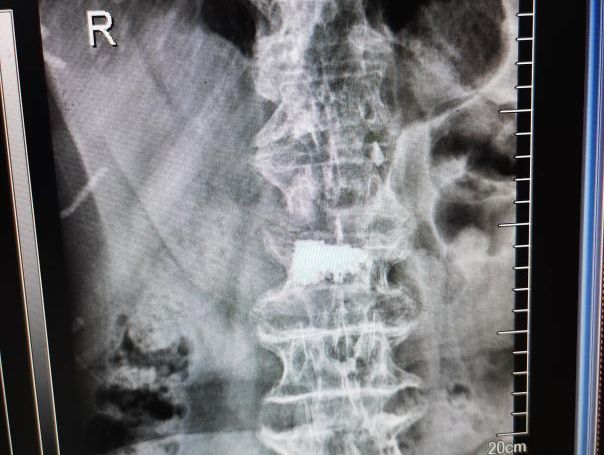

为提升区域内基层医疗机构糖尿病足诊疗服务能力、促进青年医师对糖尿病足的规范化诊治水平,遵义市第二城市医疗集团总院(贵州航天医院)圆满举办贵州省继续医学教育项目——胫骨横向骨搬移技术治疗糖尿病足专题研讨班。 贵州航天医院党委委员、副院长彭亮出席会议并致辞,遵义市第二城市医疗集团各成员单位,以及红花岗区、汇川区、绥阳县、桐梓县等多个区县的基层医疗机构骨干医师参加会议。 研讨班 本次研讨班以胫骨横向骨搬移技术在糖尿病足治疗中的应用为核心主题,围绕糖尿病药物治疗与生活方式管理策略、围手术期血糖精准调控要点、胫骨横向骨搬移技术典型病例深度解析、糖尿病足的临床分型与个体化治疗方案制定等临床实践中的热点与难点展开深入探讨,通过专题授课、案例研讨、互动交流等多元化形式,为参会者搭建了理论与实践结合的学习平台。 此次研讨班不仅为区域内基层医院搭建了学术交流与经验共享的平台,更对推动糖尿病足预防、诊断与治疗的规范化、系统化发展起到了积极作用,有效助力青年医师更新专业知识体系、提升临床技能,为进一步保障区域内糖尿病足患者的健康奠定了坚实基础。 贵州航天医院骨科专家简介 陈明勇 骨一科主任,副主任医师 临床擅长:从事创伤骨科工作约20年,对骨缺损、骨不连、骨肿瘤、肢体畸形等的肢体矫形重建及功能重建,慢性化脓性骨髓炎的根治治疗、糖尿病足的保肢治疗、快速康复理念(ERAS)下的老年骨折的诊治,四肢复杂骨折的诊治,四肢骨折等微创手术治疗具有丰富的临床经验。 2004年毕业于遵义医学院临床专业,曾在中国人民解放军总医院、广西医科大学第一附属医院、上海第六人民医院骨科进修。中国中西医结合学会骨伤科专业委员会横向骨搬移治疗糖尿病足及微血管网再生学组首届委员,遵义市医学会创伤分会常务委员。 瞿 晖 骨科党支部书记,骨二科主任,副主任医师 临床擅长:对骨科的常见病、关节外科、脊柱外科及运动医学疾病的诊治具有丰富的临床经验,熟练掌握骨科手术操作技术。 毕业于遵义医学院临床医学系,2005年前往广州中山大学第一附院骨显微医学部进修学习,2011年前往成都华西医院进修学习,并多次在省内外学习骨科相关知识,是中华医学会骨科分会会员。 赵小锋 中共党员,骨二科副主任,副主任医师 临床擅长:从事骨科临床工作11年,对骨科常见病、多发病诊疗有较为丰富的临床经验,擅长脊柱相关疾病诊断及治疗,尤其是颈、腰、腿疼痛疾病诊断及治疗,擅长胸腰椎骨折微创经皮穿刺内固定术、经皮穿刺椎体成形术、经皮穿刺脊柱内镜下腰椎间盘摘除术、单纯开创腰椎间盘摘除术、腰椎滑脱复位椎间植骨椎融合内固定术、腰椎管狭窄减压融合内固定术及人工髋、膝关节置换术等。 2012年毕业于遵义医学院外科学专业硕士研究生,2019年参加“遵义市115医学人才精英计划”于上海交通大学第一附属医院培训学习,2023年于北京大学第三人民医院脊柱外科进修学习,曾获得遵义市优秀医师荣誉称号。 遵义市手外科第一届委员,遵义市医学会创伤分会第一届委员,遵义市医学会创伤分会第二届委员,贵州省康复医学会第三届脊柱脊髓专业会委员,遵义市医学会烧伤与整形外科学分会委员,发表论文5篇,其中国家级核心期刊1篇,SCI论文1篇,主持市级课题1项并结题,参与市级课题2项。 赵兴东 骨科主任医师 临床擅长:擅长骨科的常见病及各种创伤、四肢骨折创伤修复、骨感染、手足疾病的诊治和手足体表畸形的矫形整复,熟练掌握骨科四肢骨病及创伤的手术操作技术,尤其在四肢关节复杂性损伤、手足外伤、组织缺损创面、难治创面的皮瓣修复方面及平足、高弓足矫形方面及四肢慢性疼痛诊治、康复方面具有丰富的临床经验。 硕士研究生,毕业于遵义医学院临床外科系,2015年前往山东省立医院手足外科进修学习;遵义市医学分会创伤分会第一、二届委员,遵义市手外科医学会第二委届员会常务委员;在省级及省级以上期刊发表文章9篇,参编著作2部,参与主持并完成市级课题1项,参与市级课题2项、省级课题1项。 张艳金 中共党员,骨科副主任医师 临床擅长:从事骨外科工作16年,对复合伤、多发伤的救治、四肢骨干骨折、关节周围骨折、骨肿瘤、骨髓炎等诊治具有丰富的临床经验。 中共党员,硕士研究生,2006年本科毕业于山西医科大学第二临床医学院,2011年研究生毕业于北京军区总医院;在“老年COPD患者合并髋部骨折的诊治”国际合作课题组研究两年,在老年髋部骨折的诊治方面具有丰富的经验,并发表论文6篇;主持遵义市级课题1项,承担遵义医科大学的临床教学工作,获得遵义医科大学优秀带教老师荣誉。编撰有《骨科疾病诊疗精粹》一书,开展2项新技术,编撰地方规范《务川自治县创伤骨科常见疾病诊疗规范》一书。 张俊凯 骨科副主任医师 临床擅长:从事骨科临床工作28年,对创伤骨折、骨感染、骨缺损、骨不连等外科诊治,四肢骨折的微创手术治疗,四肢复杂骨折(如关节内粉碎性骨折、多发骨折等)的损伤控制及手术治疗等具有丰富的临床经验。 1995年毕业于遵义医学院临床专业,2009年前往复旦大学附属医院骨科进修1年。 卢懿明 中共党员,骨科副主任医师 临床擅长:从事骨科工作18年,对创伤骨折、四肢骨折的微创手术治疗、四肢复杂骨折(如关节内粉碎性骨折、多发骨折等)的损伤控制及手术治疗,尤其是髋部骨折的PFNA等微创技术,踝关节骨折、膝关节周围骨折的Mipo微创技术等具有丰富的临床经验,开展了4项新技术,发明6项新型专利技术。 2005年毕业于遵义医学院临床专业,2017年,前往南方医科大学第三附属医院骨科进修半年,回院后运用Mipo技术对骨干骨折及干骺端骨折的治疗技术,同时积极开展骨盆骨折、髋臼骨折腹直肌外侧切口的应用;发表了多篇专业论文,经常参与省内外学术交流会授课,获得医院荣誉称号多个。 邬夏荣 骨科副主任医师 临床擅长:从事骨科工作16年,对四肢复杂骨折、骨肿瘤的诊治,尤其是足踝创伤、慢性踝关节损伤、平足症等诊疗具有丰富的临床经验。 2006年毕业于遵义医科大学临床医学专业,曾在陆军军医大学西南医院进修学习,发表多篇骨科学术论文。 余德怀 中共党员,骨科副主任医师 临床擅长:从事骨科工作10余年,对运动医学、骨关节、脊柱外科常见病、多发病的诊治具有丰富的临床经验。 硕士研究生,2011年毕业于遵义医学院临床医学专业,曾前往遵义医科大学附属医院运动医学专业进修学习;是贵州省医学会运动医学分会青年委员,西部关节镜联盟委员;发表多篇骨科学术论文。 冯 乾 骨科副主任医师 临床擅长:从事骨科工作近20年,熟练掌握骨科多发病及常见病的诊治,尤其对脊柱退变性疾病的诊断及治疗具有丰富的临床经验,主要研究脊柱微创相关治疗方式,能熟练开展椎间孔镜及UBE。 曾前往北京大学第三医院进修学习疼痛及椎间孔镜、首都医科大学友谊医院专业进修脊柱内镜;是贵州省康复医学会第三届脊柱脊髓专业委员会委员;发明专利3项、发表脊柱外科专业论文多篇。 贵州航天医院骨科简介 基本情况 贵州航天医院(原3417医院)骨科组建于1968年,前身是以创伤和断肢(断指)再植闻名于世的上海市第六人民医院骨科,中国断肢(断指)再植的奠基者、中科院院士陈仲伟等专家莅临科室指导医疗和教学,并在70年代开展了贵州省首例断肢(断指)再植手术。组建50余年来,诊治患者已逾百万,挽救了无数的伤病员,成为了保障遵义地区人民群众健康的重要支撑。 经过几代人的不懈努力,今天的骨科,已由创伤骨科发展至骨病、骨肿瘤、骨结核等领域,现有脊柱外科、关节外科、四肢创伤、手足外科四个亚专科,成为了集医疗、教学、科研于一体的综合学科,是贵州省临床重点专科、遵义市临床重点专科、遵义市骨科临床医学中心、遵义市基层骨科专科联盟理事长单位。 科室目前开放床位110张,共有医护人员50余人,副高级以上专家18人,硕士研究生15人。拥有一流骨科医疗设备多台,每年不定期选派优秀技术骨干到全国各大知名医学院校进修、学习、参观、交流,并邀请国内、国外知名专家教授来院进行交流、指导,通过不断引进国内外先进的诊疗技术,科室医疗技术水平稳步提升,为广大人民群众提供了优质的医疗服务。 专科特色 骨一科 (一)骨缺损、骨不连的肢体与功能重建 胫骨横向骨搬移技术治疗糖尿病足: (二)慢性骨髓炎的根治治疗 (三)肢体缺血性疾病如糖尿病足、脉管炎的保肢治疗 (四)皮瓣修复 (五)复杂创伤的治疗 (六)老年髋部骨折及小儿骨折快速手术 老年髋部骨折: 骨二科 (一)胸腰椎骨折微创经皮椎弓根螺钉固定术 (二)老年性骨质疏松性患者腰椎滑脱脊柱内固定术(骨水泥螺钉) (三)V形双通道脊柱内镜技术(VBE)腰椎融合术治疗腰椎退行性疾病 (四)老年性骨质疏松性骨折(PVP/PKP)术 (五)人工髋关节置换术 (六)双侧股骨头坏死人工全髋关节置换 (七)右侧全髋置换术后假体周围骨折翻修 (八)人工膝关节置换术 (九)人工膝关节假体松动翻修 (十)关节镜技术 传统手术切口 关节镜技术切口 诊疗范围 骨一科 1.四肢创伤、矫形。 2.手、足踝外科。 骨二科 End